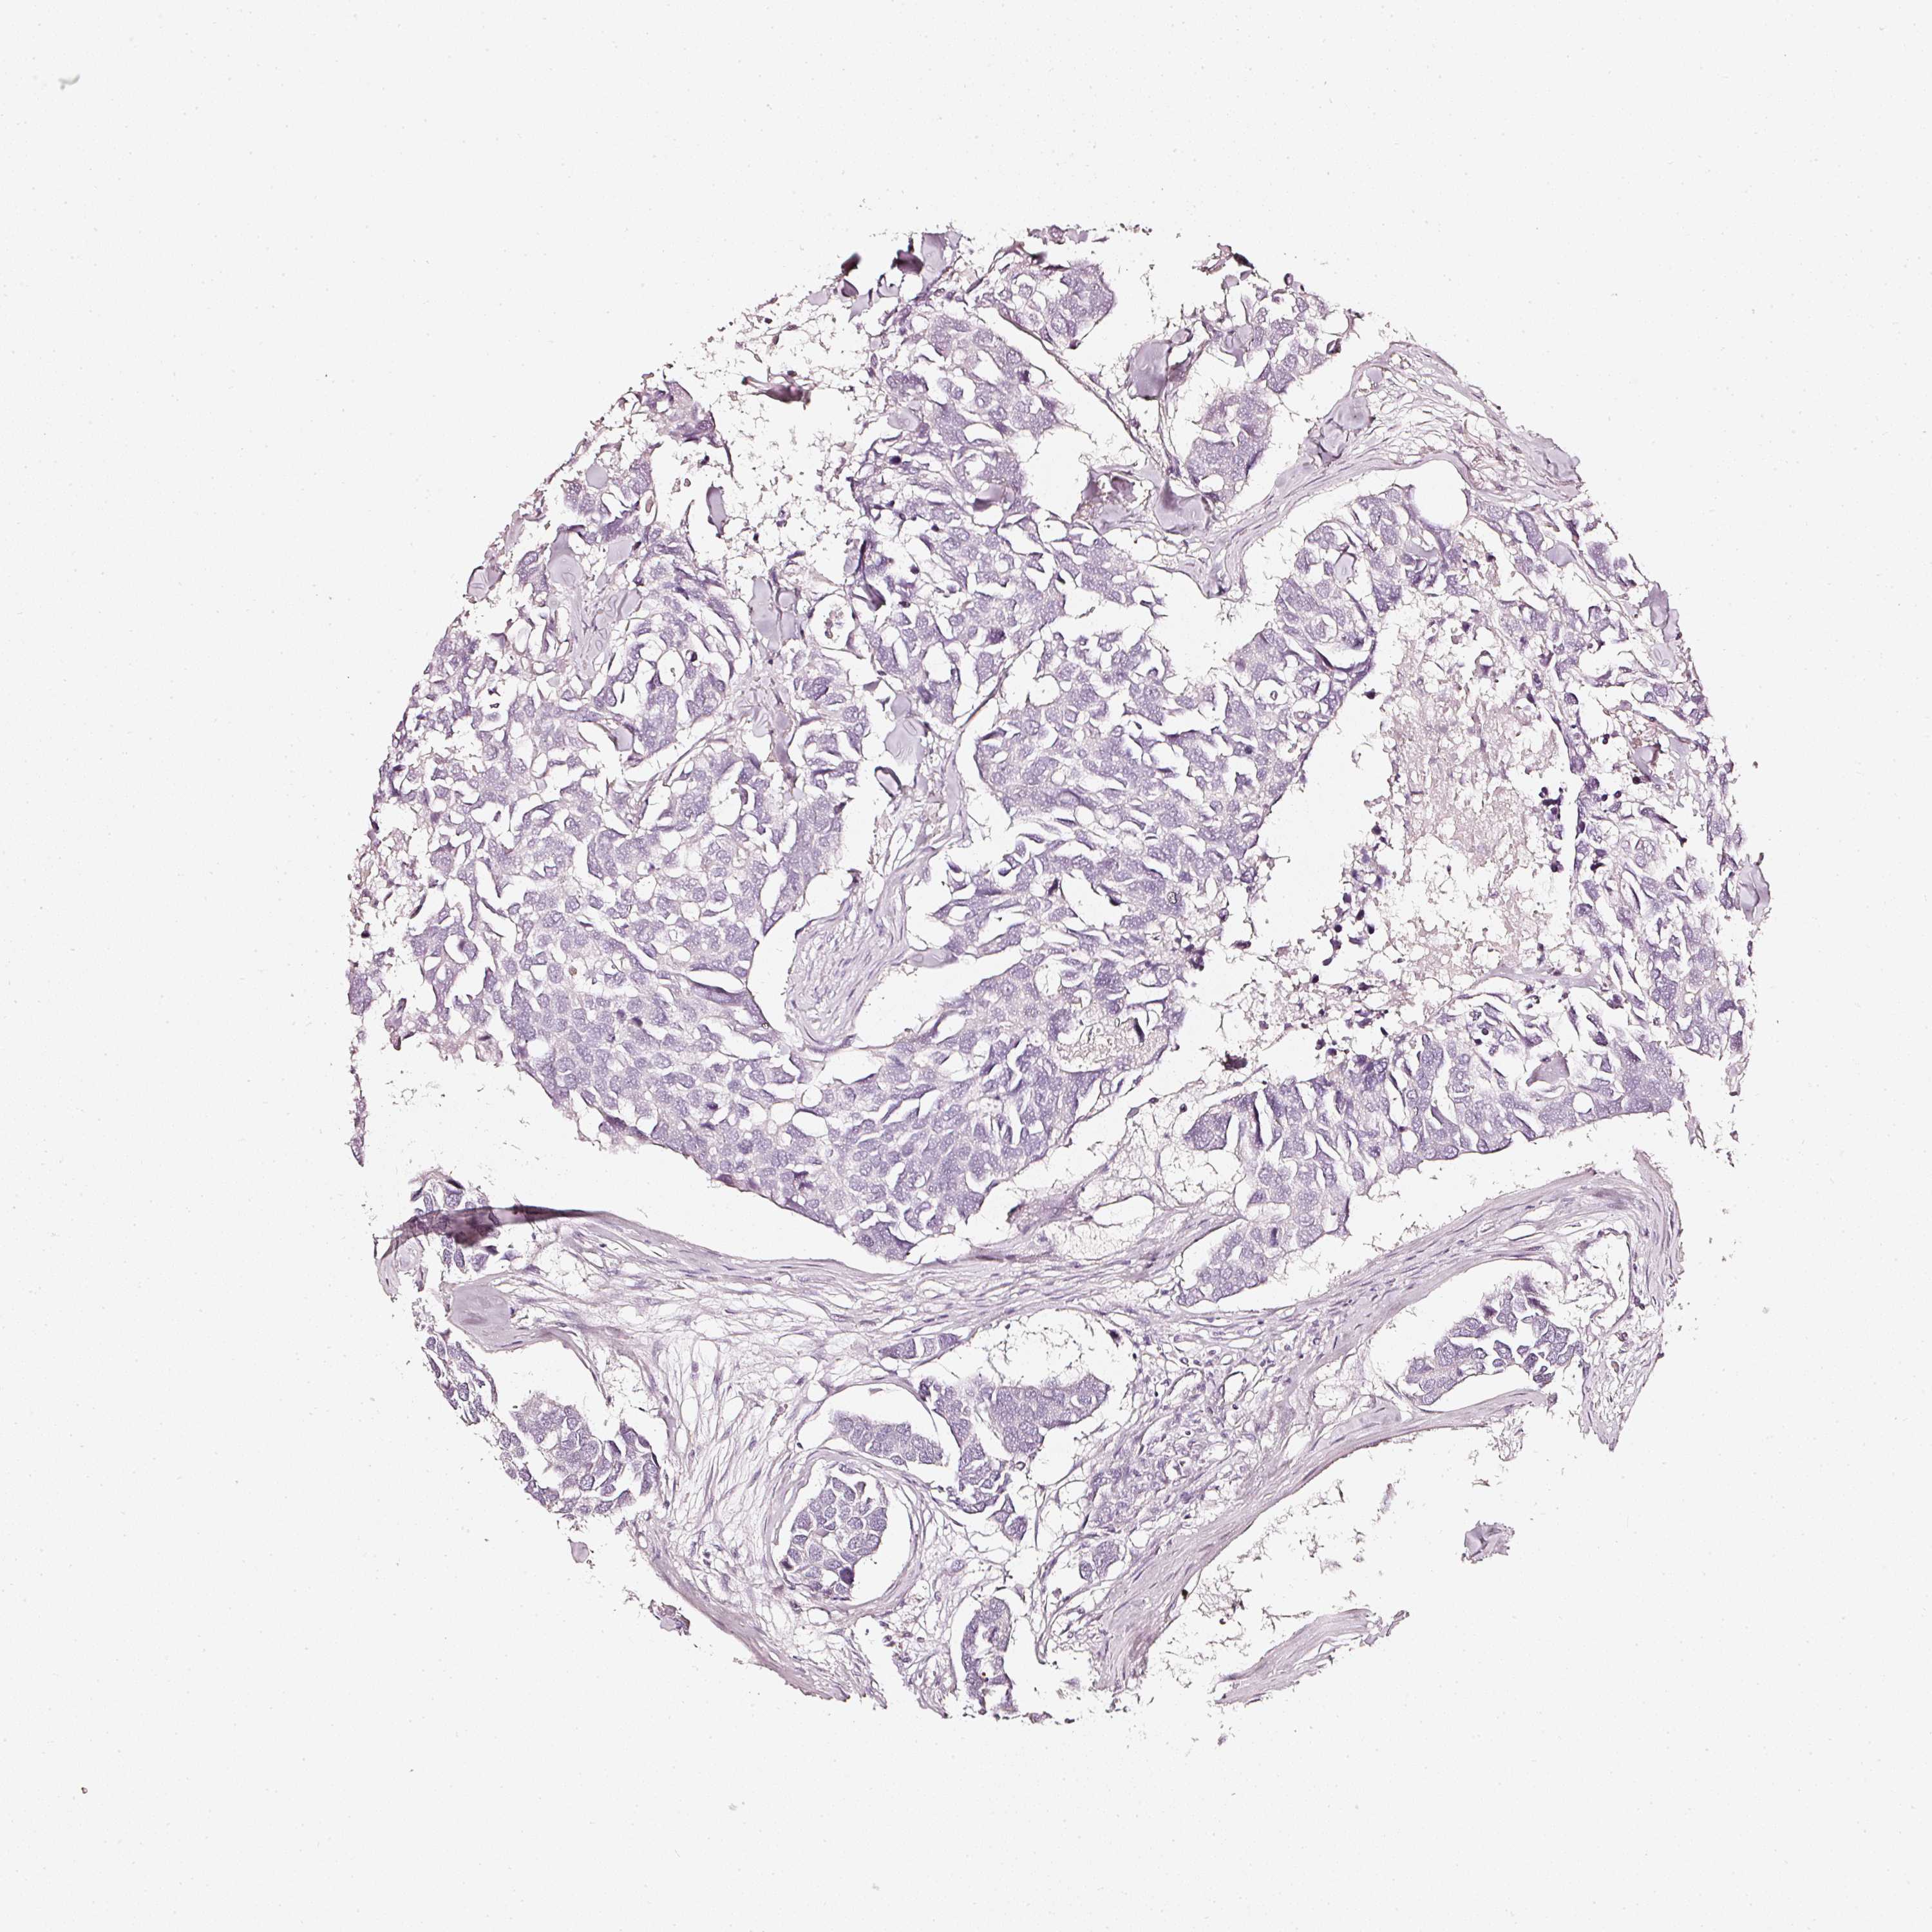

BRCA TCGA BRCA VALIDATION PROTEIN EXPRESSION

ANTIBODIES

AND

VALIDATION